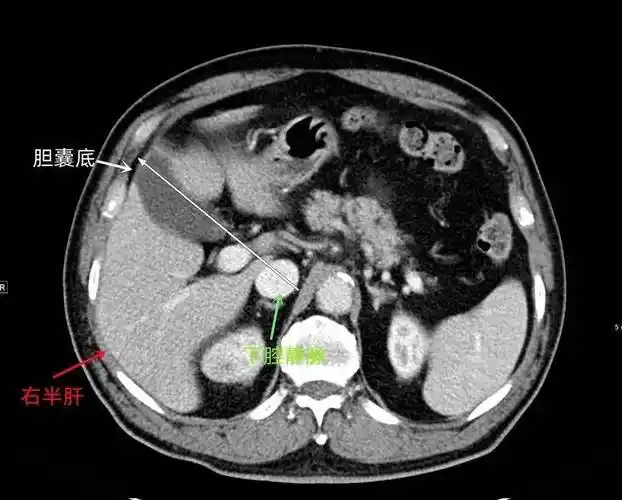

超赞!最全肝脏的表面解剖及分叶分段

couinaud肝脏分段系统ct图谱

结合解剖看腹部ct,轻松掌握肝脏读片!_静脉_水平_脏器